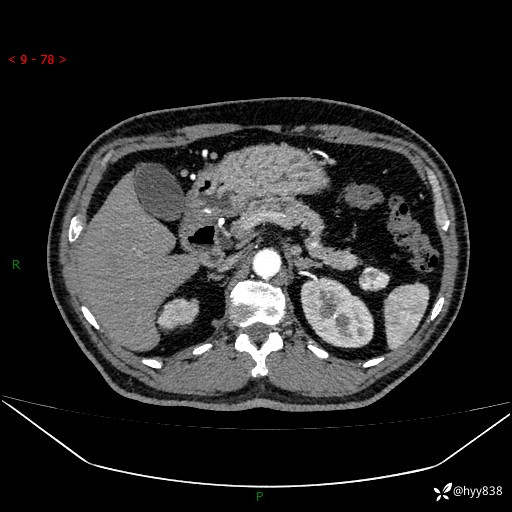

静脉期